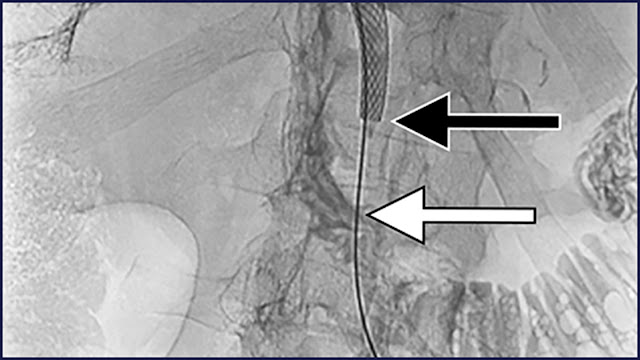

Figure

A self-expanding metallic stent was placed with its lower margin (black arrow) above the level of the sphincter (white arrow).

A single-center retrospective study of 54 patients with inoperable perihilar cholangiocarcinoma who underwent percutaneous transhepatic biliary stent placement between January 1, 2019, and August 31, 2021, was conducted. According to stent location, the patients were classified into 2 groups: suprapapillary (S) and transpapillary (T). Demographic data, Bismuth-Corlette classification, type and location of the stent, laboratory data, postprocedural AEs, procedural success, stent occlusion, reintervention rate, and mortality were compared between the groups.

Stent placement was suprapapillary in 13 (24.1%) patients and transpapillary in 41 (75.9%) patients. Mean age was higher in Group T (78 vs 70.5 years; P = .046). Stent occlusion rates were similar in the 2 groups (Group S, 23.8%; Group T, 19.5%), as were AE rates, the most common being cholangitis (Group S, 23.1%; Group T, 24.4%). There were no significant differences in revision rate (Group S, 7.7%; Group T, 12.2%) and 30-day mortality rate (Group S, 15.4%; Group T, 19.5%). Ninety-day mortality rate was statistically significantly higher in Group T (46.3% vs 15.4%; P = .046). Preprocedural bilirubin level was higher in Group T, as were postprocedural leukocyte and C-reactive protein (CRP) levels.